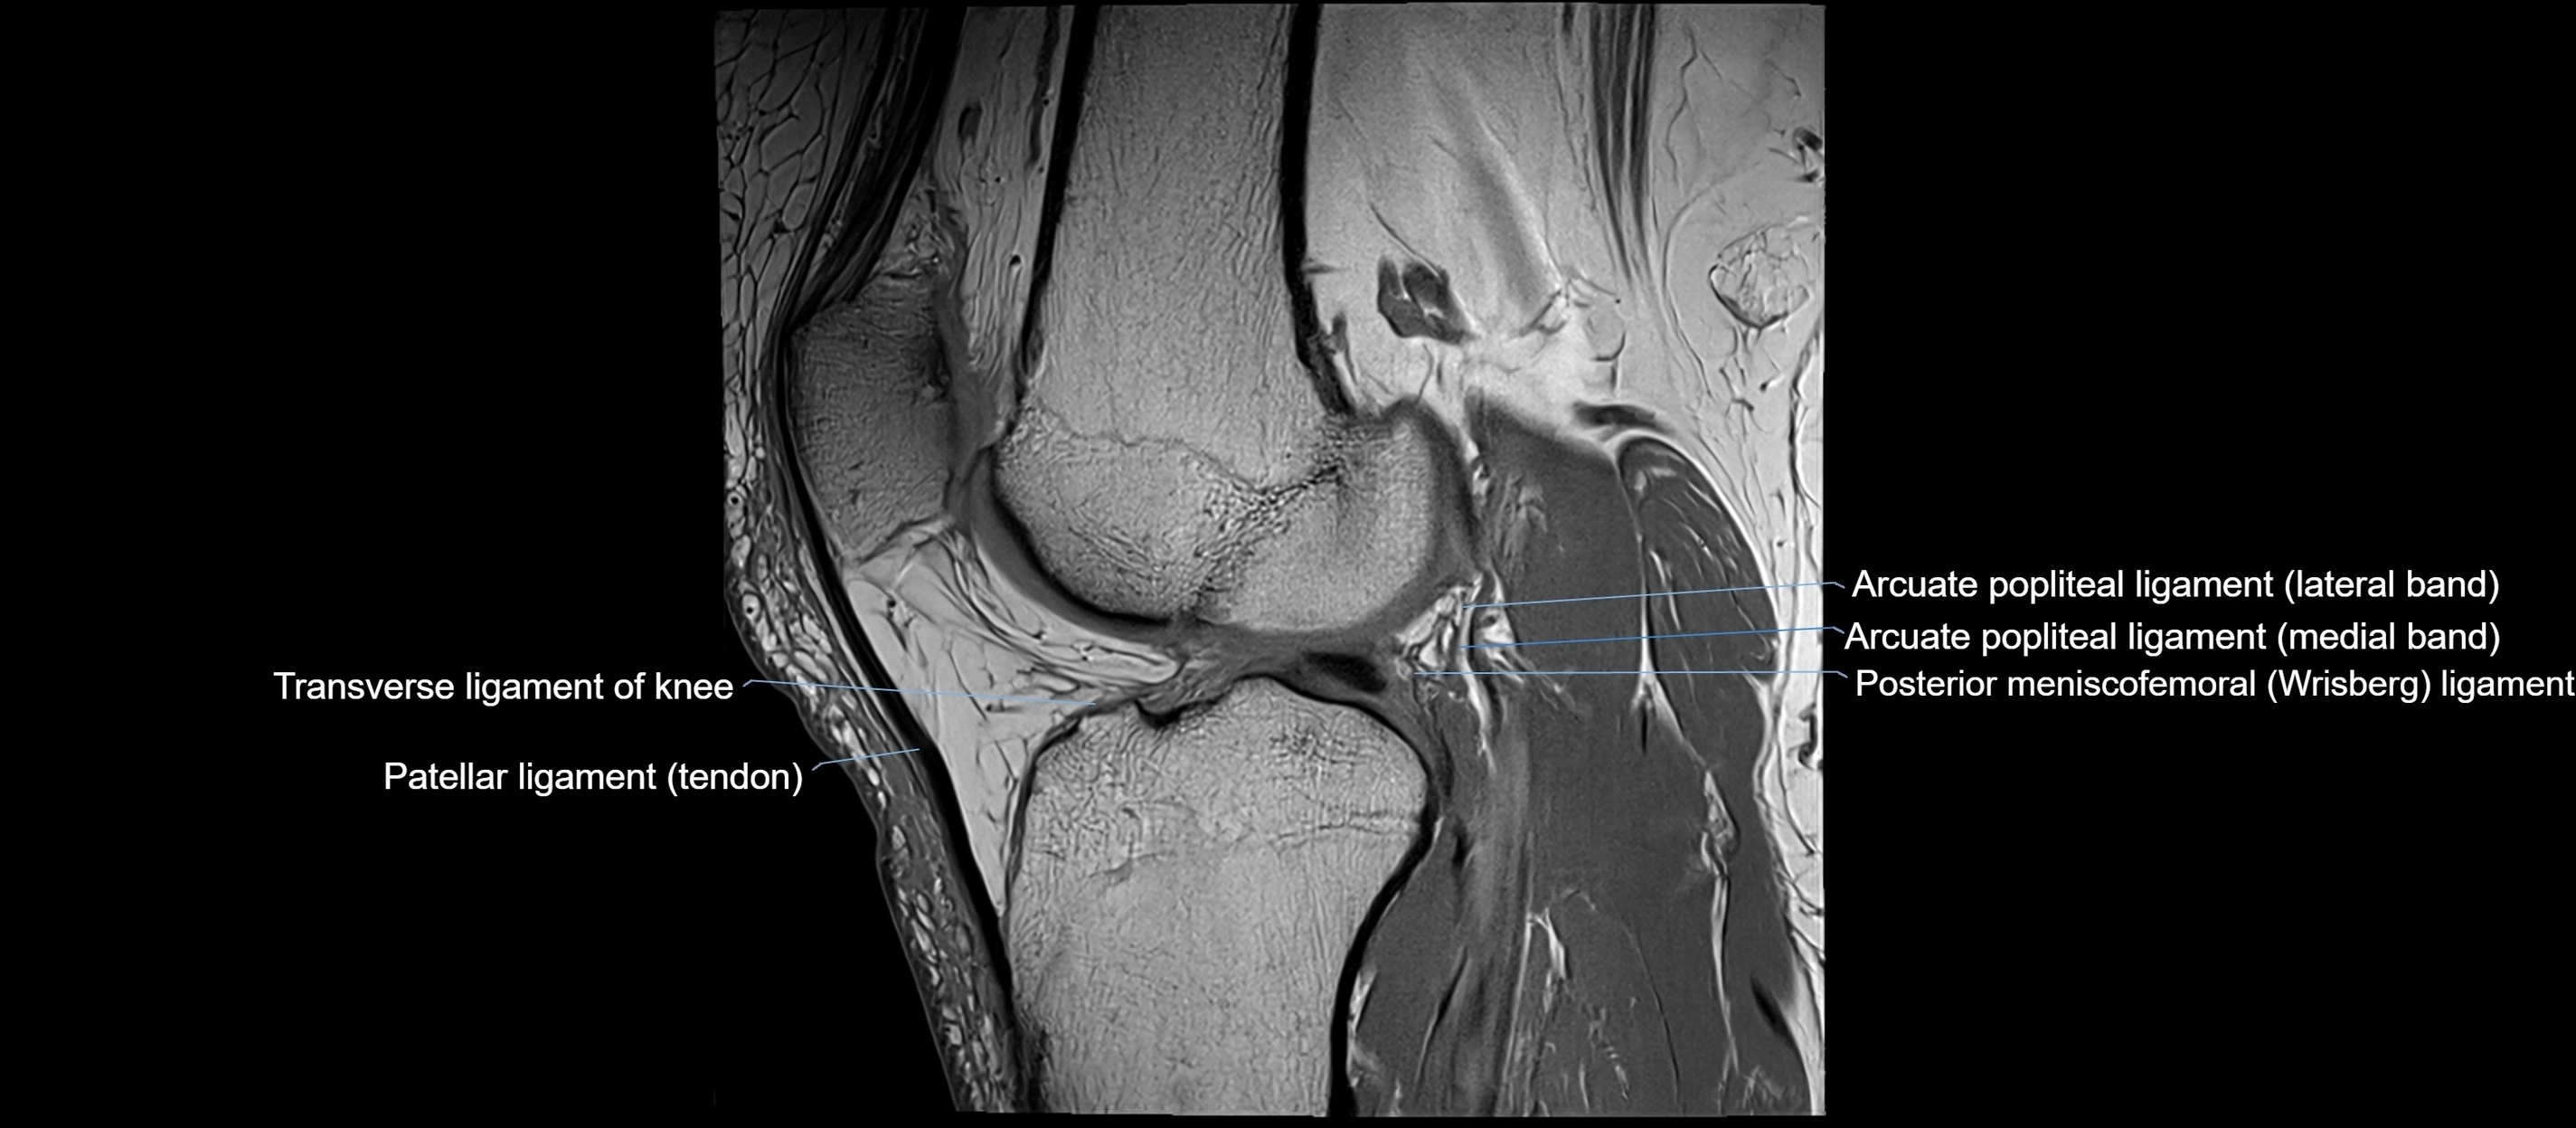

MRI images

image